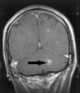

Chagas disease, also known as American trypanosomiasis, is a tropical parasitic disease caused by Trypanosoma cruzi. It is spread mostly by insects known as Triatominae, or "kissing bugs". [Source: Wikipedia ]